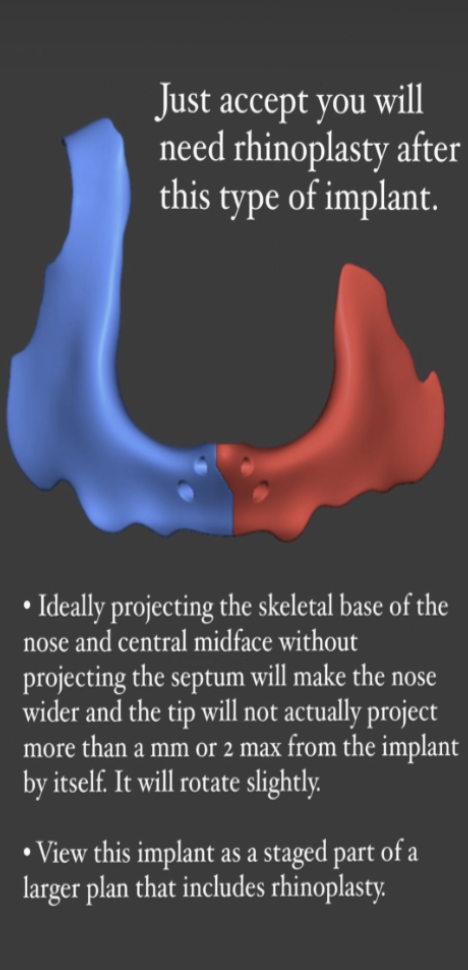

- Implant desgined to mimic the pointiness of the ANS. The implant projecfts the ANS forwards along with the nose base.

- Can be superior to grafting as it provides better contour and results are more predictable.

- This can increase the projection of the septum by 2 mm max according to giant.

- Recommended to be placed during rhinoplasty. Can be placed during bimax as long as it doesnt block the plates, but this is not recommended and can yield unfavorable results.